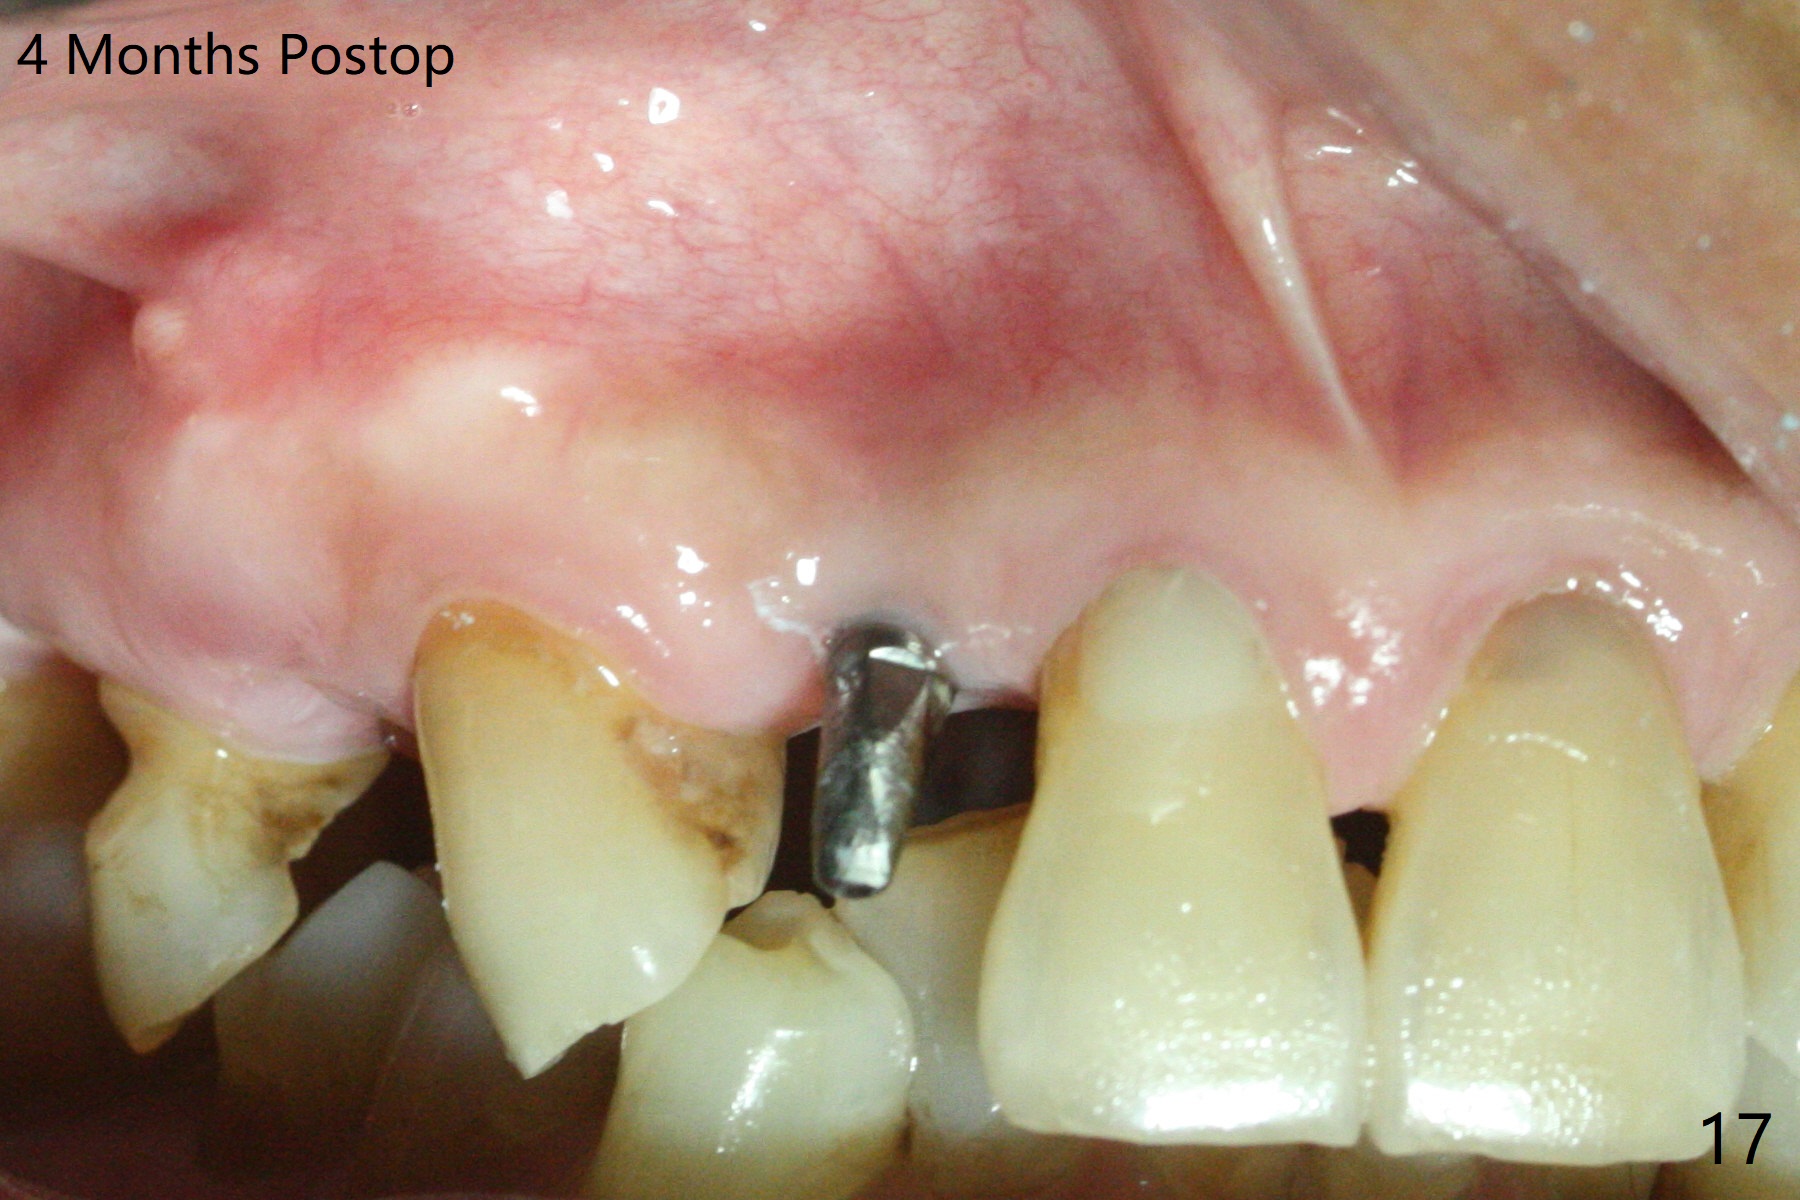

An apical abscess is present when the patient returns for immediate implant at #7 (Fig.1 *); a 2nd challenge is deep bite. After smooth extraction, the apical buccal plate is found to be perforated. Following debridement, a piece of gauze is placed in the apical defect for hemostasis, while osteotomy is initiated palatal (Fig.2). The apical defect seems to be extensive (Fig.3 yellow dashed line). A new trajectory is intended (red arrow) without much success. Before implant placement, bone graft is placed in the apical defect defect area, while a drill (Fig.4 D) is inserted in the finished osteotomy (Fig.5 O). In spite of seemingly large apical defect, the buccal crest bone exists (Fig.4 x). A 3x14(2) mm 1-piece implant is placed with stability; the first round of bone graft is apparently around the apical portion of the implant (Fig.6 *). The coronal end of the implant has to be adjusted several times buccopalatally to accommodate the deep bite. A 2nd round of bone graft following an immediate provisional closes the coronal space of the socket (Fig.7 *). CT will be taken to show the bone graft to repair the buccal plate defect when the patient returns for postop follow-up. In fact the defect is minimal in CT a month ago. The fistula does not disappear 1 week postop, but it is non tender (Fig.8). The patient complains of asymptomatic swelling in the right nostril. CT shows that the large buccal perforation is repaired with large amount of bone graft (Fig.9,10 *). It would be nicer to place the implant slightly more buccal apically (Fig.11 red lines; Fig.12 (preop design)). The buccoapical fistula disappears nearly 1 month postop (Fig.13). The apparently "lifeless" bone graft seems to be harmonious with the surrounding tissue (Fig.14). The periimplant gap reopens with implant mobility nearly 4 months postop (Fig.15), which is related to micro-movement associated with the immediate provisional. The latter is removed. A larger 2-piece implant will be placed in a 2-staged manner if needed (Fig.16). In fact the 3x14 mm straight 1-piece implant (Fig.17) has no mobility when it is retightened, but the trajectory remains buccal. Incision shows that there is no implant thread exposure. A 3x14 mm 15 degree angled 1-piece dummy implant is able to establish the correct trajectory, but there is no occlusal clearance (Fig.18). Micromovement during osteointegration may recreate loosening. Finally using Lindamann bur, the osteotomy is changed so that a 3.5x13 mm 2-piece implant does not need an angled abutment to establish occlusion (Fig.19). There is one palatal thread exposure. Allograft is placed circumferentially, followed by Human Amnion-Chorion Allograft and Collagen Plug. The wound does not heal 8 days postop (Fig.20), as related to the age (79 years old)? The wound appears to heal with a membrane on the surface (Amnion-Chorion one?) 3 weeks postop (Fig.21). The ridge looks wide 3.5 months postop (Fig.22,23). A 4.5x5.5(3) mm appears to be seated incompletely with a gap between the abutment and the implant (Fig.24<). A provisional is fabricated after heavy palatal reduction. Two months later, the provisional fractures. After repositioning the abutment with complete seating and torque (Fig.25), impression is taken. Although the buccal plate is concave, the gingiva remains healthy 10 months post cementation (Fig.26,27).